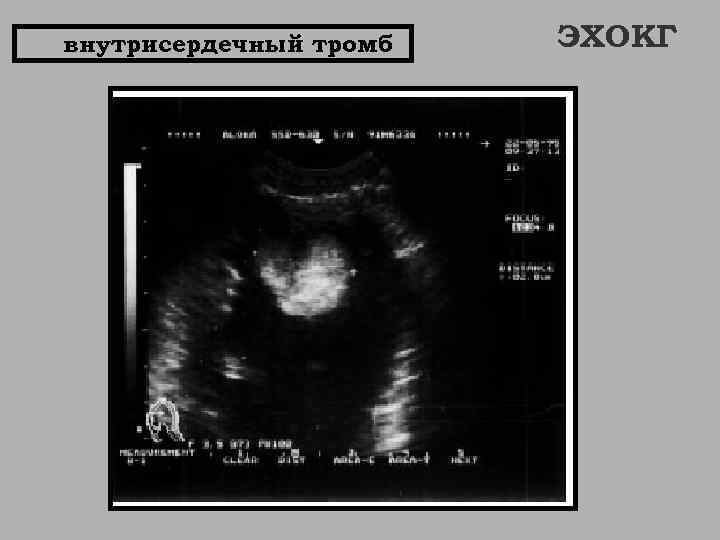

внутрисердечный тромб ЭХОКГ